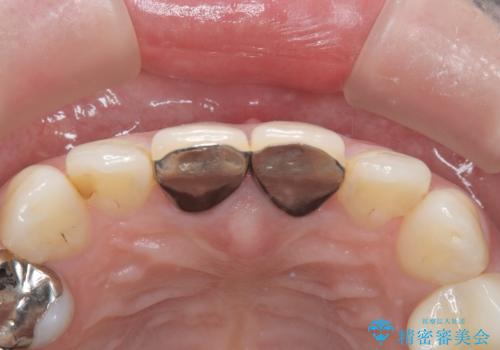

- 前歯の変色を主訴に来院されました。

根管治療、土台のやりかえも提案しましたが、金銭的理由より、クラウンのみの修復としています。

今後痛みが出た場合は、外科的歯内療法での対応を希望されています。